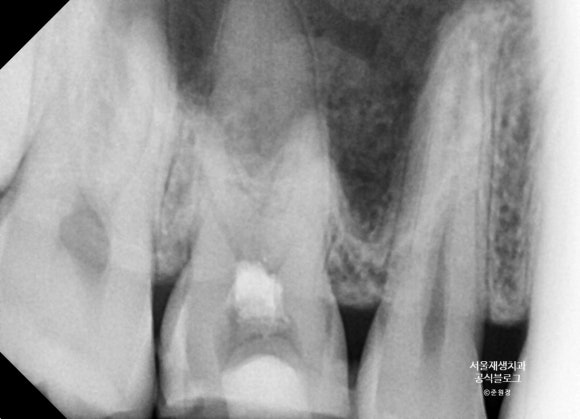

간혹, 윗어금니의 뿌리가 너~~무 길어서 상악동까지 뻗어나가고 있는 경우가 있습니다.

뿌리가 정말 길어서 사진 한 장에 담기지가 않는군요.

머리 부위와 뿌리 부위를 나누어서 촬영했습니다.